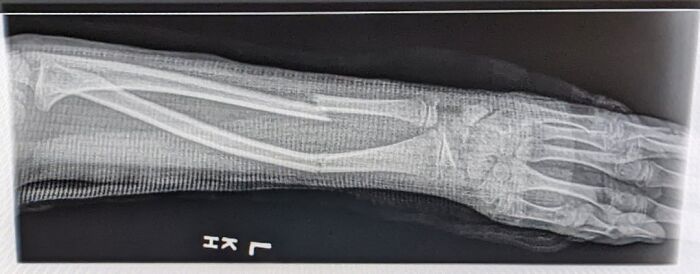

#37 My 9 Year Old Daughter Broke Her Arm. The Doctor Said She Will Heal Fine. Should I Get A Second Opinion?

Image source: medical